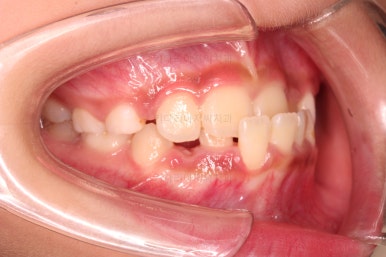

치료 한 달 째 사진인데요.

벌써 반대교합이 많이 좋아지고 있습니다.

턱의 위치도 좋아지고, 많이 :삐뚤었던 앞니도 일정 부분 위치가 좋아지고 있습니다.